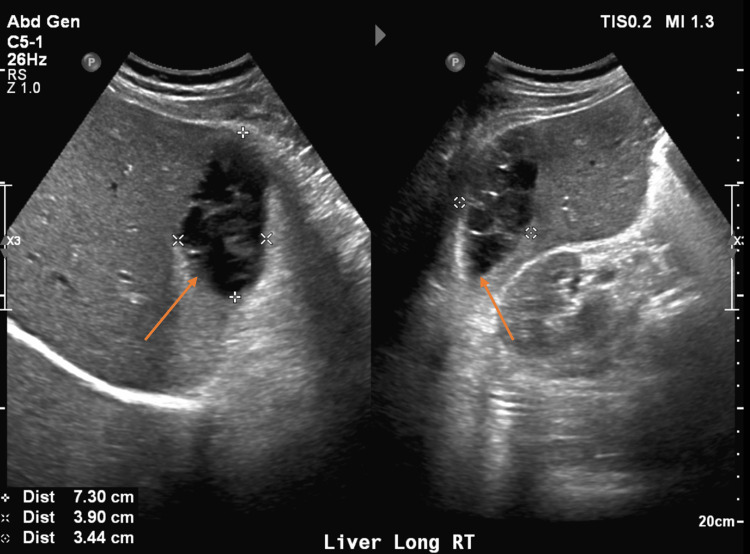

On arrival, he was afebrile and vital signs were unremarkable. Physical exam was significant for epigastric and RUQ tenderness to palpation with voluntary guarding but a soft abdomen without rebound tenderness. Laboratory findings were significant for white blood cell (WBC) count of 10.8 (reference range [RR] 4.5 to 11.0 × 109 L-1), alkaline phosphatase (ALP) of 117 (RR 44-147 International Units/L), hemoglobin (Hgb) 11.7 (RR 14.0 – 17.5 g/dL), which was at baseline. Bilirubin and transaminase levels were within normal limits. Abdominal ultrasound (AUS) demonstrated an area of mixed echogenicity on the right side of the liver measuring 7.3 cm × 3.9 cm with marked dilation of the common bile duct (CBD) and intrahepatic biliary tree (Figure 2), slightly decreased when compared with earlier imaging. A triple-phase CT scan of the abdomen and pelvis (A/P) was significant for a 9 cm × 6.5 cm × 2.5 cm heterogeneous, high-density collection in the subcapsular segment 6 of the liver without rim enhancement, likely representing a hematoma, as well as persistent CBD dilation of 13 mm (Figure 3). He was initially managed with conservative treatment, including Piperacillin-Tazobactam, intravenous fluids (IVFs), and pain control. His WBC count trended down. Piperacillin-Tazobactam was subsequently discontinued due to a lack of fever, leukocytosis, and other clinical signs of infection.